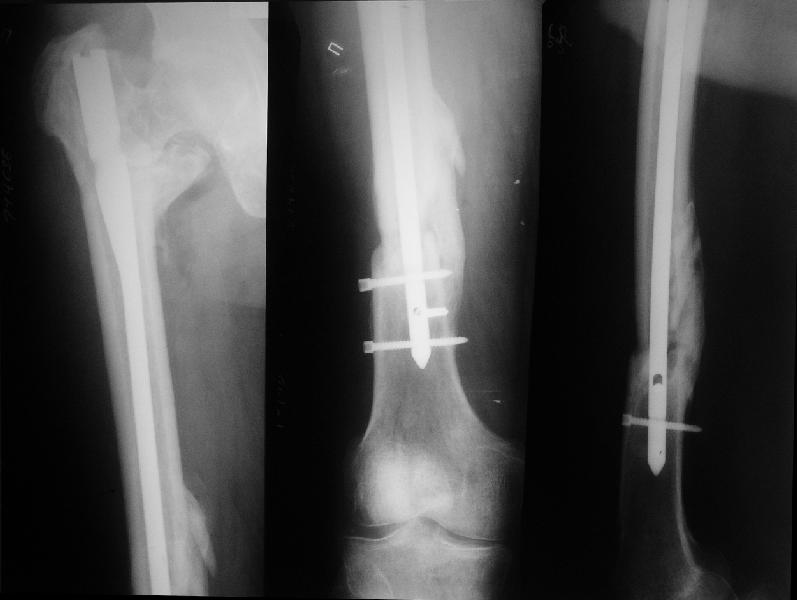

На прошлой неделе оперировали похожего пациента. 2 года после неудачного остеосинтеза PFN в другом регионе. После удаления остатков железа выявилось несращение вертельной области.

В такой ситуации важно устранить варусную деформацию. При использовании гвоздя это непросто. Поэтому в число рассматриваемых

вариантов стоило бы включить вальгизирующую остеотомию с фиксацией 130-градусной клинковой пластиной или DHS.

Если есть сильное желание фиксировать все-таки гвоздем, советовал бы ввести мощный "джойстик" параллельно оси шейки бедра близко к ее задней стенке, сделать поперечную межвертельную остеотомию и использовать дистрактор таз-бедро.

Поскольку в нашем случае выявилась подвижность, мы наложили дистрактор таз-бедро на 3 дня, и сделали остеосинтез гаммой без остеотомии. То, что произошла "корригирующая остеоклазия" в подвертельной области, выявили после введения гвоздя. Пациент уже уехал домой, будем наблюдать.